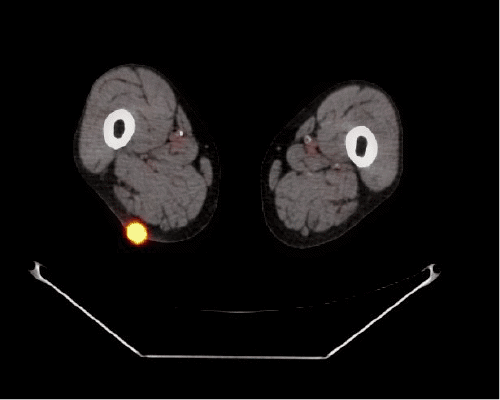

Following a minor procedure, the patient received pathology results. A tumor board discussion at the VAMC determined the need for further staging, leading to a PET/CT scan in which multiple foci of FDG activity were identified in the chest, abdominal wall, and bilateral thighs. To facilitate chemotherapy, a port was placed in September 2019. The patient then underwent palliative FOLFOX chemotherapy, achieving an initial response. Unfortunately, the disease progressed, and the patient passed away in August 2020.

Figure 1. PET/CT Demonstrating FDG-avid Activity in Soft Tissues. Published With Permission

In our case, the skeletal muscle metastases were the first indication that his esophageal adenocarcinoma, which had been treated almost four and a half years earlier, had recurred. His subsequent PET/CT scan demonstrated additional areas of FDG-avidity that were not clinically apparent, underlining the role of these advanced imaging modalities. We elected to remove the symptomatic lesions as a palliative measure.